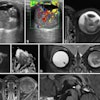

Back at the WFUMB congress, there was plenty of discussion about hepatic imaging. Firstly, evidence was presented about how contrast-enhanced ultrasound can help to characterize liver disease. Click here for our article.